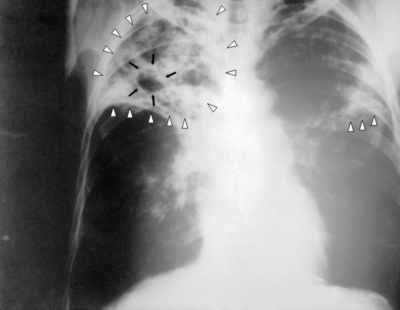

Hoje sabemos que o bacilo de Koch é um longínquo companheiro da evolução humana. Já existindo muito antes dos nossos primeiros ancestrais hominídeos, seguramente até antes dos primeiros mamíferos, o M. tuberculosis adaptou-se espantosamente ao tecido pulmonar humano. De tal forma que o pulmão é o seu albergue por excelência, o seu paraíso microbiano, e é muito difícil combate-lo uma vez ali instalado.